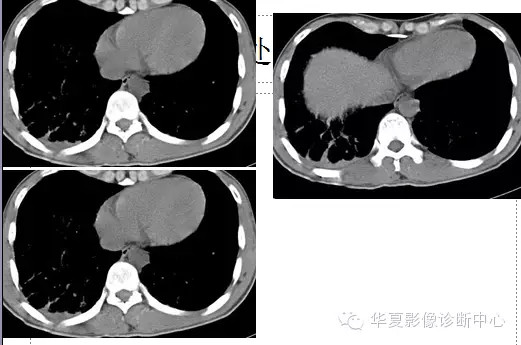

两肺野弥漫性分布的斑点及斑片状阴影,呈“暴风雪”样,病变以两中下肺野为多,部分小叶间隔增厚,心脏大小正常。纵隔窗显示右侧胸腔后下部少量积液。。

诊断:肺脂肪栓塞综合征。